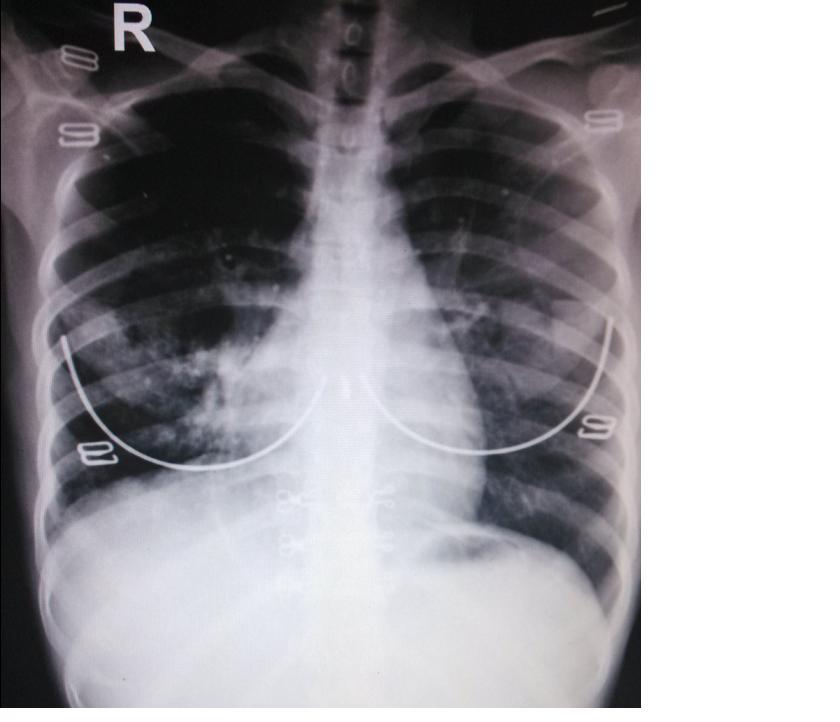

咱们平时不需要*光脱**做检查,是因为大多数情况下,穿的衣服不影响片子的质量。但是有些衣服是的确是会的。比如这样:

X线就像安检机,什么东西都能看到个大体形态。比如雨伞,茶杯,电脑,但是在人体检查的时候要求精确,就不能有遮挡。之前我也遇到过,看似病人肺部有个结节,紧张了很久,其实就是衣服胸前口袋里的拉链头。